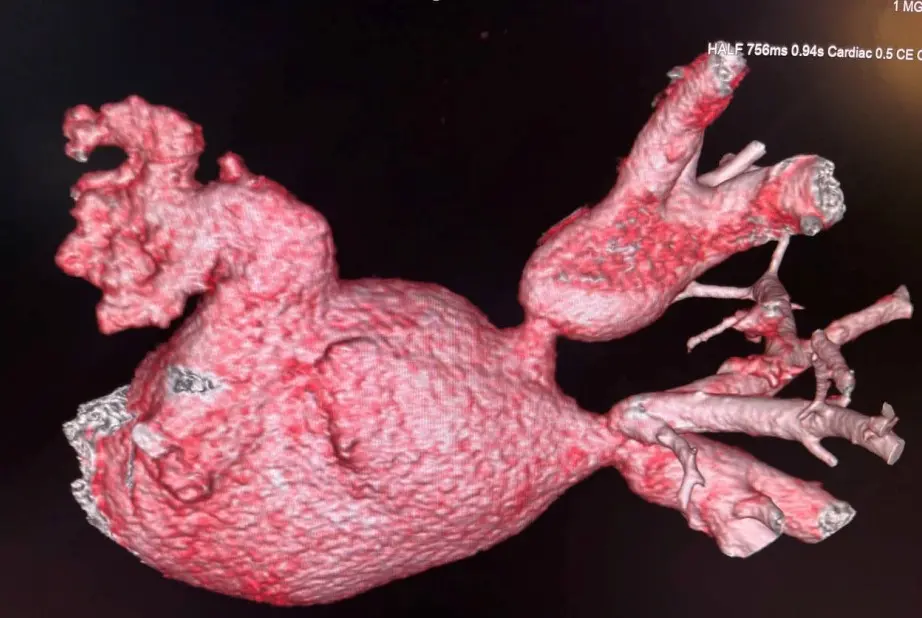

Рисунок 1. МСКТ 3d реконструкция левого предсердия

Пациент М., 54 лет наблюдался с длительной историей нарушений ритма сердца. Ранее ему была выполнена криоабляция, а спустя два года — радиочастотная абляция. Через два месяца после РЧА у пациента появились выраженная слабость и одышка при физической нагрузке. При дообследовании выявлены окклюзии левой верхней и левой нижней легочных вен.

С учётом тяжести состояния и высокого риска дальнейшего прогрессирования заболевания было принято решение о проведении эндоваскулярного восстановления проходимости легочных вен. Стентирование одновременно двух легочных вен является технически крайне сложным вмешательством и требует высокой экспертной подготовки. Подобные операции выполняются в ограниченном числе специализированных центров и НМИЦ кардиологии им. ак. Е.И. Чазова Минздрава России располагает наибольшим в стране опытом лечения данной категории пациентов.